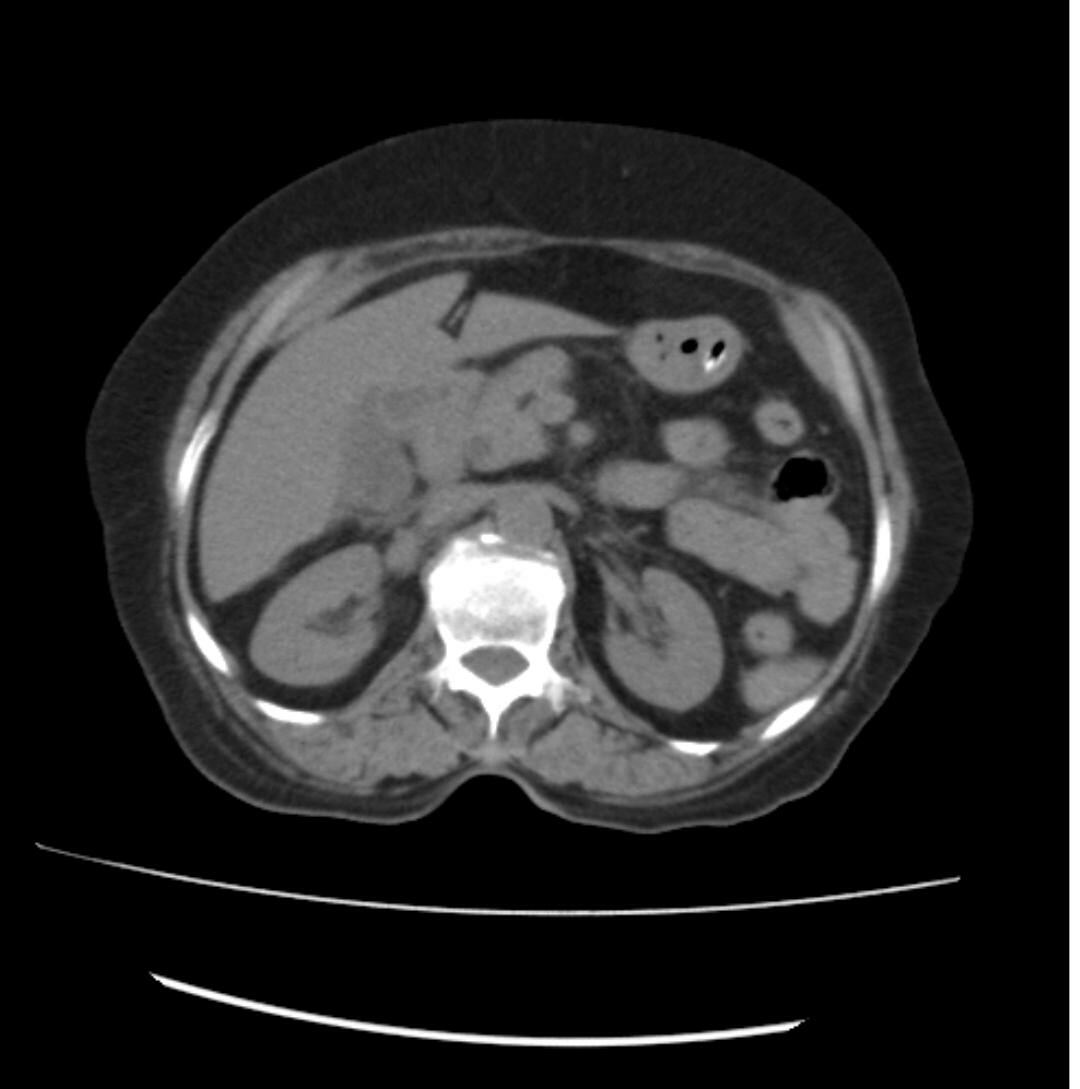

CECT

USG- GB wall edema

No cholelithiasisi /percholecytic fluid

Body of pancreas  homgenous hetero cholic

17 mm fatty uninfiltration

B/L Grade 1 RPD

Grade 1 fatty liver disease